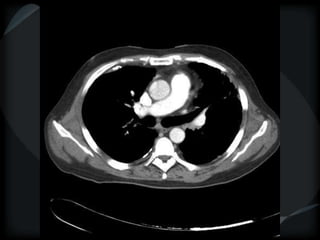

PHTN – PA 39mm

39.2mm

PHTN and septal thickening

? PVOD